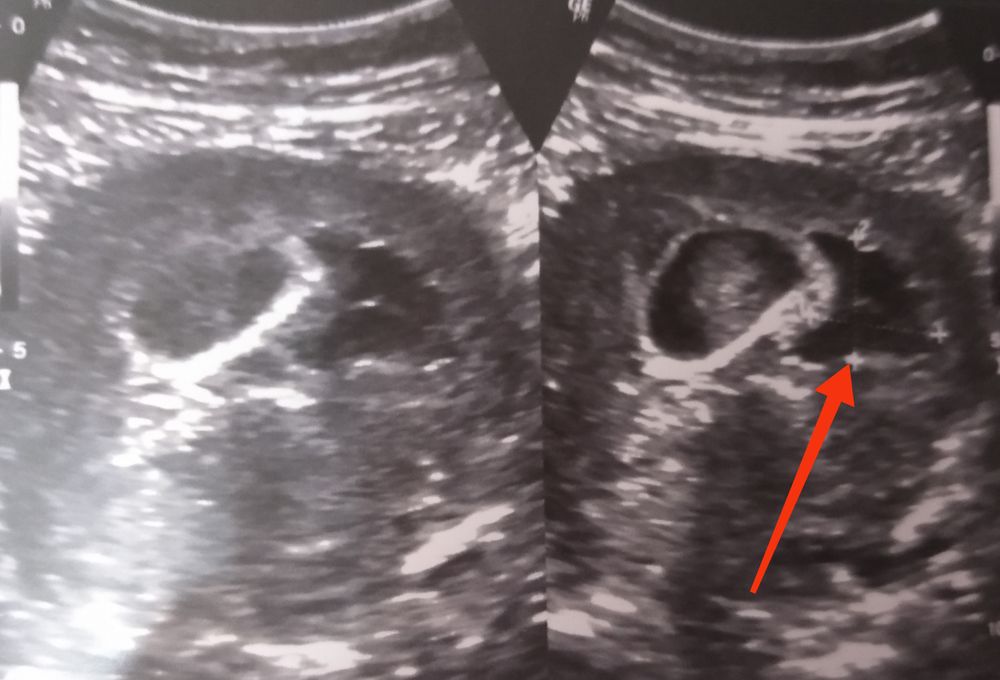

В жк и стационаре тоже писали ретрохориальная гематома , тоже увеличилась за неделю , но ре опроверг , сказал плацента подрастет и эту кровяную жидкость расплющит, это физиологический процесс, а гематома это сгусток его у меня нет , думаю у Вас тоже самое, не волнуйтесь. Выделений не было .

Виолетта, о! Спасибо за фото. А то везде гематома выглядит не такой черной.

Сальма♥МЕБЕЛЬ♥Орматек♥38Попуг, гематома в кавычках, ре сказал это не гематома )) в жк писали 1×0,6 , через неделю с сильным токсикозом легла в стационар 3×0,6 через4 дня при выписке 2,3×0,4 , как сказал ре это жидкость она не будет постоянной формы и размера , и через 2 -3 недели когда плацента поднимется её вообще не видно будет